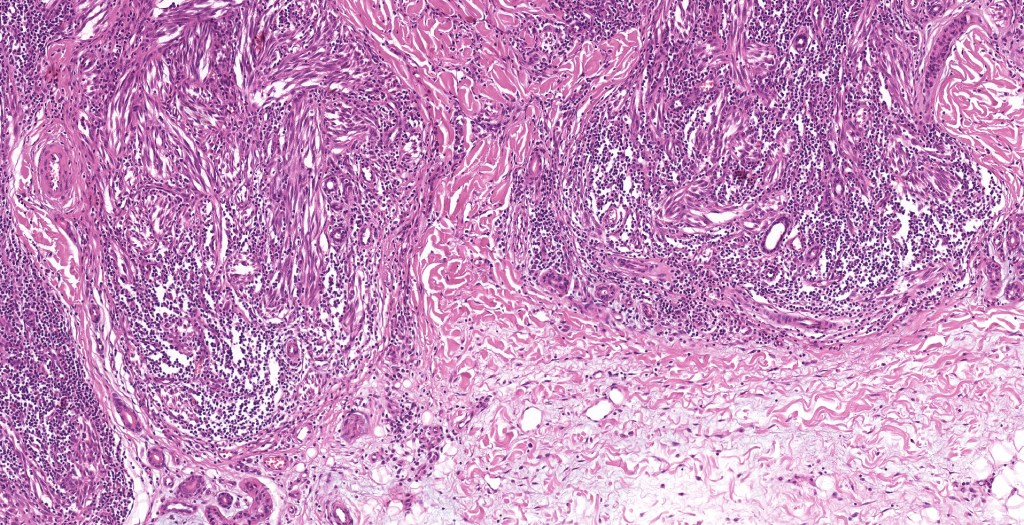

•Sharply circumscribed (begins and ends with a nest), symmetrical dome-shaped lesion. Symmetry is both horizontal and vertical (see image below)

•Wedge-shaped with the base uppermost or sometimes plaque-shaped silhouette

•Matures with depth-often best recognized at scanning/low power magnification & readily confirmed with S100 or MART1

•Maturation implies nest size and cell size diminishing with depth, at the base, the infiltrate may have a single cell infiltrating pattern

•Hyperkeratosis & acanthosis, sometimes very marked

•Superficial vascular ectasia very frequently present

•Lymphocytic infiltration at the base of the lesion